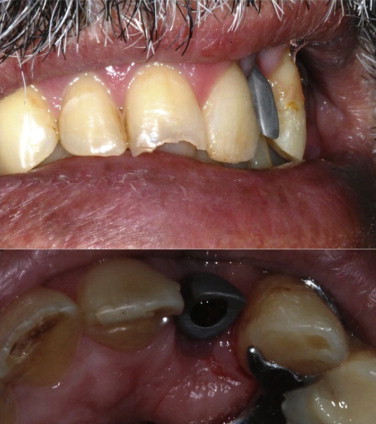

After the metal casting (Figs. 6 and 7), the setting of the coping was assessed through radiographs so the ceramic cover could be applied (Fig. 8). On the next session, a prosthesis try-in was performed, the occlusal and proximal contacts were evaluated with a carbon paper (Accufilm II, Parkell, New York, USA) and, with the patient’s informed consent, the prosthesis was finalized.

Fig. 6.

Healthy gum margin around metal casting.

Fig. 7.

Metal casting of the prosthesis.

Fig. 8.

Prosthesis aspect after the ceramics application.

At the installation moment, the dental contacts were once again verified, as was the radiographic aspect (Fig. 9), a 20 N torque was applied to the abutment screw and, in a different session, the screw access hole was covered with a resin composite. The patient was pleased with the final clinical aspect (Figs. 10 and 11).

Fig. 9.

Radiographic image after the prosthesis installation.